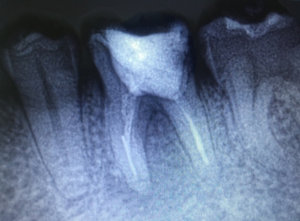

4 месяца назад мне сделали вкладку на предпоследний зуб нижней челюсти, при этом рядом стоящий ближний зуб удалили, т.к. было нагноение на десне. Я не сделала коронку на один зуб, т.к. хотела закрыть просвет и от недостающего зуба. Но и стачивать ближний зуб (здоровый) мне не хотелось. На дорогой имплант средств не нашлось. Сейчас зуб со вкладкой стал побаливать и на десне снова появилось нагноение. Из-за чего это произошло и что мне теперь делать? Явилось ли моё промедление результатом нагноения или это могло произойти и под коронкой?

Добрый день . Конечно это произошло бы и под коронкой, так что не мучайте себя. Дело в самих каналах, вернее в плохо пролеченных каналах, что повлекло обострение воспалительного процесса.